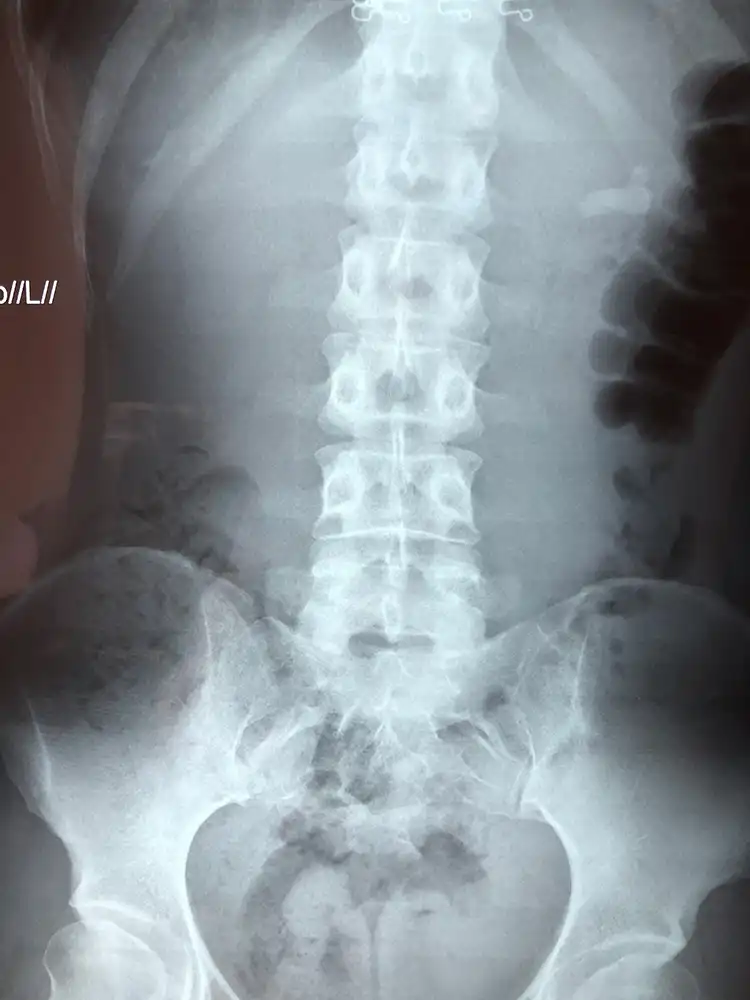

Περιστατικό 1, Ημιάκαμπτη Ουρητηρολιθοθρυψία (semi-rigid URS)

Ασθενής με ευμεγέθη λίθο στο άνω τριτημόριο του αριστερού ουρητήρα, ο οποίος φέρει νεφροστομία λόγω αποφρακτικής ουροπάθειας (Φωτογραφία 1), αντιμετωπίστηκε με laser ουρητηρολιθοθρυψία με ημιάκαμπτο ουρητηροσκόπιο και τοποθέτηση pig-tail με ταυτόχρονη αφαίρεση της νεφροστομίας (Φωτογραφία 2, 1η ημέρα μετεγχειρητικά). Η τρίτη φωτογραφία είναι στις 15 ημέρες πριν την αφαίρεση του pig-tail.